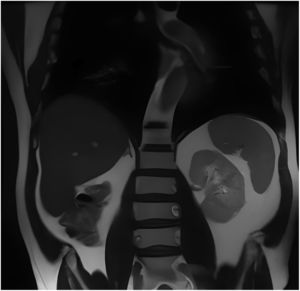

Posteriormente, fue tratado quirúrgicamente, confirmándose una metástasis de 11 mm en su diámetro mayor, sin invasión renovascular ni perineural, con bordes de sección libres de tumor. Se realizó una resonancia magnética de tórax, cerebro y abdomen sin signos de enfermedad metastásica secundaria (fig. 3). Finalmente, se inició el manejo del cáncer con inmunoterapia con pembrolizumab, con buena tolerancia y respuesta.